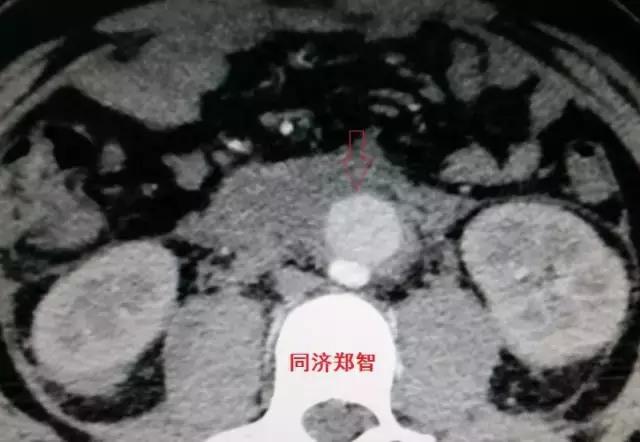

病例十一

平扫CT发现主动脉血管内孤立的钙化点(红色箭头所示),CTA证实为降主动脉溃疡合并壁间血肿。

病例十二

平扫CT提示降主动脉一接近外周的钙化点(红色箭头所示),CTA证实为降主动脉壁间血肿。